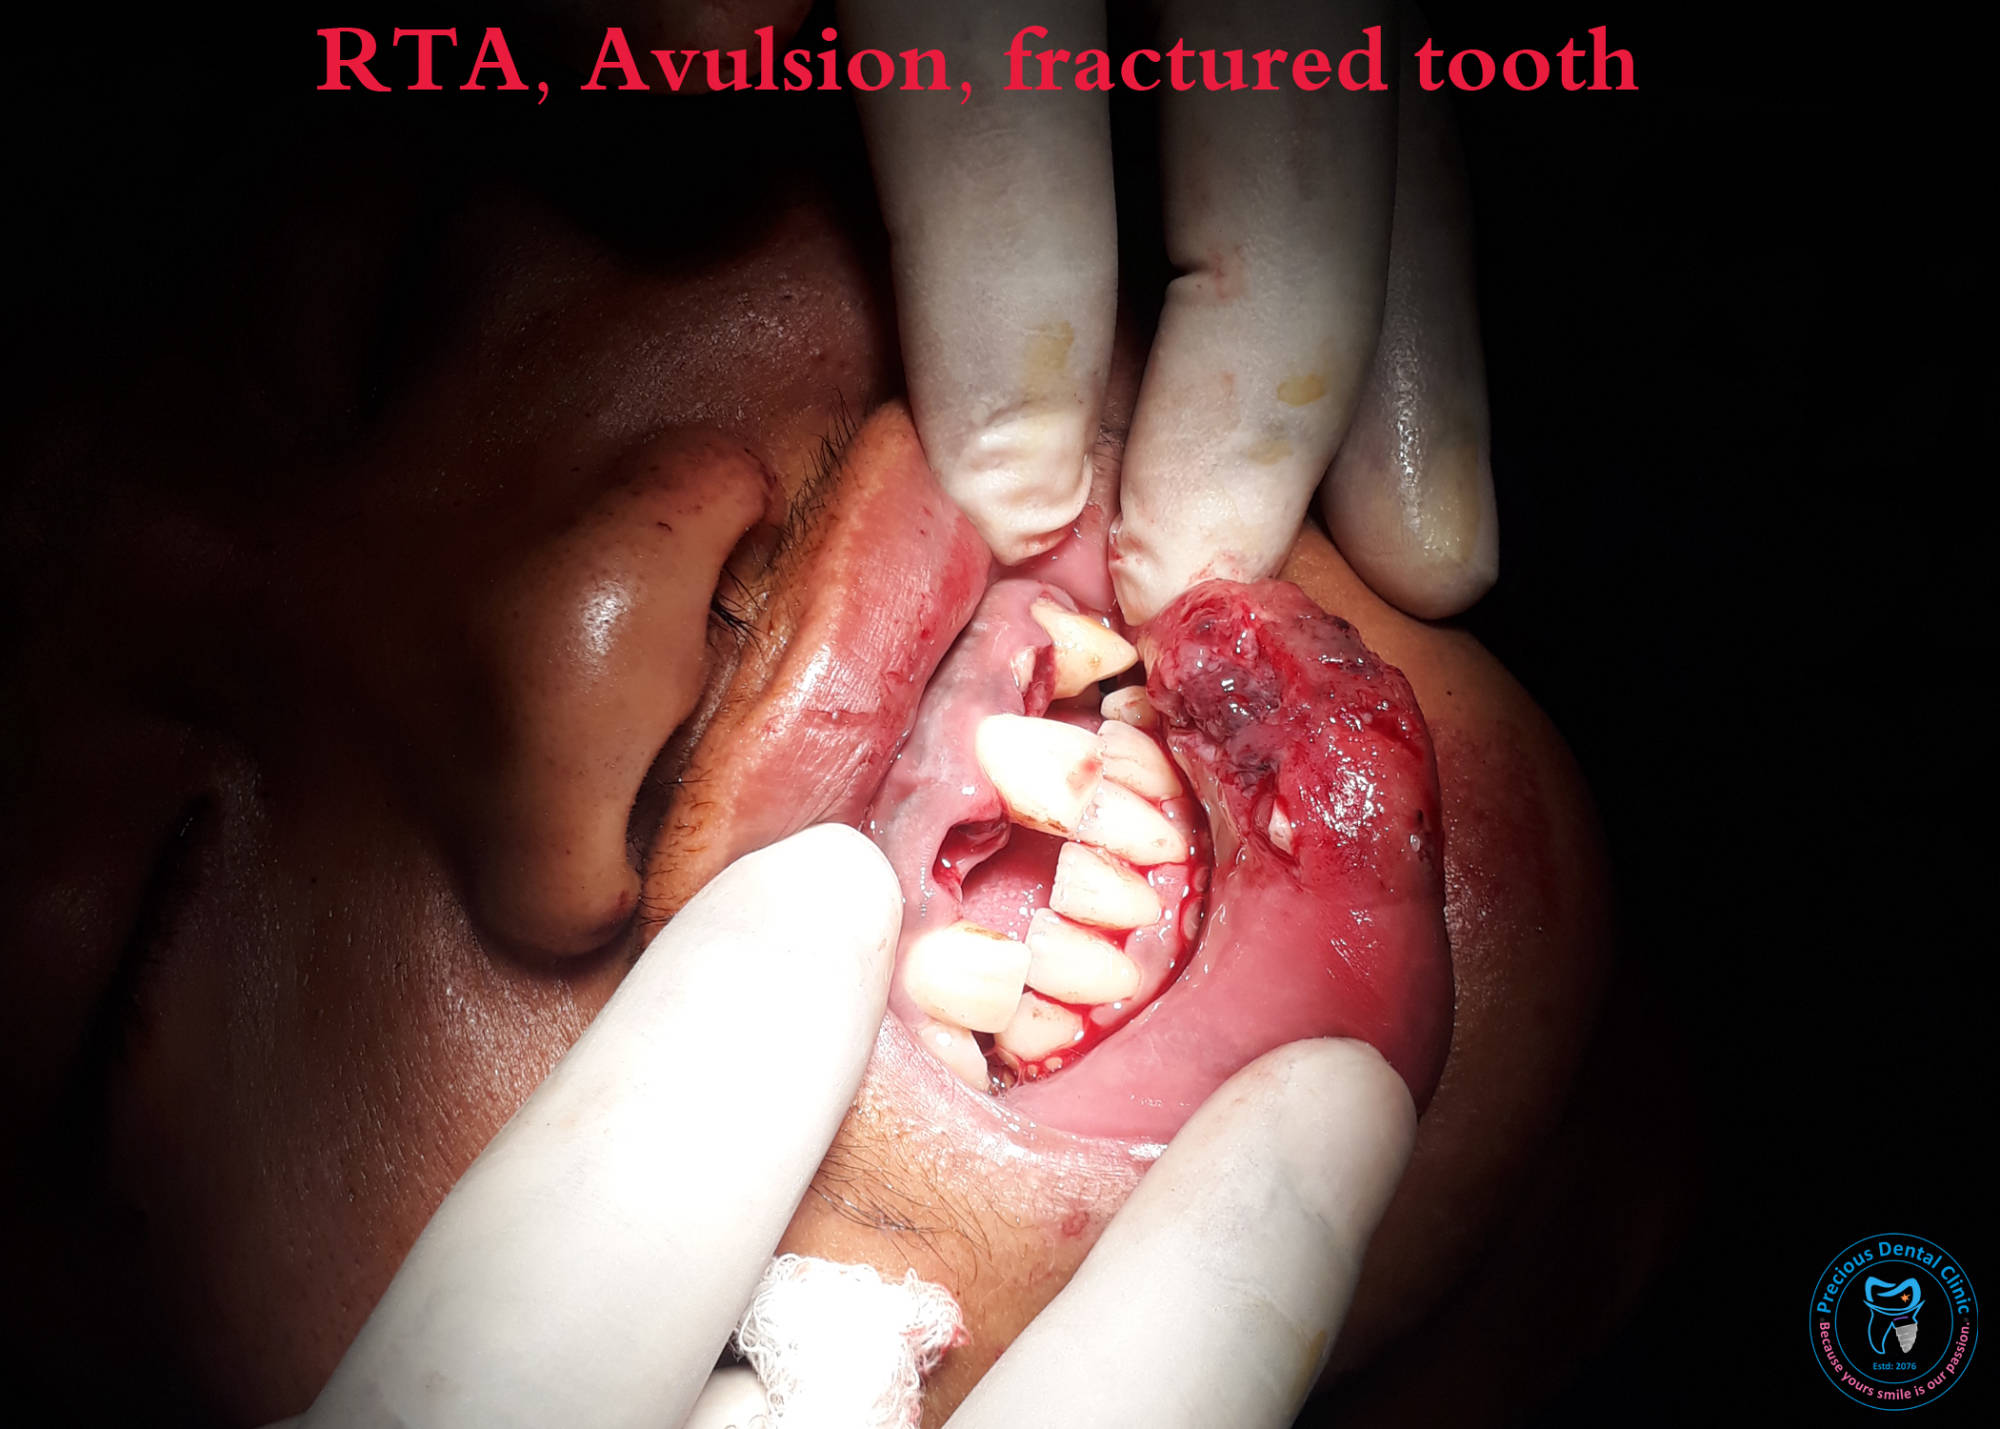

Ulcer Avulsion

Avulsion Bite Injury

Supenumery Tooth IOPAR RTA

RTA Supenumery Tooth 2